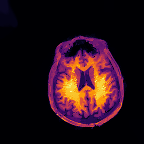

Multi-modality (or multi-channel) imaging is becoming increasingly important and more widely available, e.g. hyperspectral imaging in remote sensing, spectral CT in material sciences as well as multi-contrast MRI and PET-MR in medicine. Research in the last decades resulted in a plethora of mathematical methods to combine data from several modalities. State-of-the-art methods, often formulated as variational regularization, have shown to significantly improve image reconstruction both quantitatively and qualitatively. Almost all of these models rely on the assumption that the modalities are perfectly registered, which is not the case in most real world applications. We propose a variational framework which jointly performs reconstruction and registration, thereby overcoming this hurdle. Numerical results on simulated and real data show the potential of the proposed strategy for various applications in multi-contrast MRI, PET-MR, and hyperspectral imaging: typical misalignments between modalities such as rotations, translations, zooms can be effectively corrected during the reconstruction process. Therefore the proposed framework allows the robust exploitation of shared information across multiple modalities under real conditions.